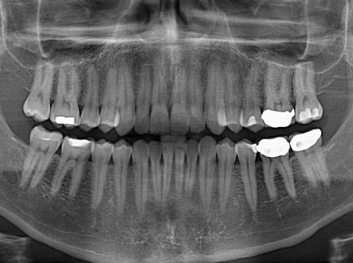

Adam Celiz,是來自諾丁漢大學(xué)的研究人員,他和同事開發(fā)的這種新型合成生物材料,能刺激干細(xì)胞在牙髓部的生長。與普通材料一樣,這種合成材料被填充到牙齒并用UV光硬化。

在體外測試中,材料刺激干細(xì)胞進(jìn)入牙本質(zhì)的增殖和分化速度,促進(jìn)形成牙齒骨組織。研究人員認(rèn)為,一旦材料在受損牙齒中應(yīng)用,這些干細(xì)胞可以自動修復(fù)來自填充物上的損壞。在本質(zhì)上,該生物材料將使牙齒自愈。